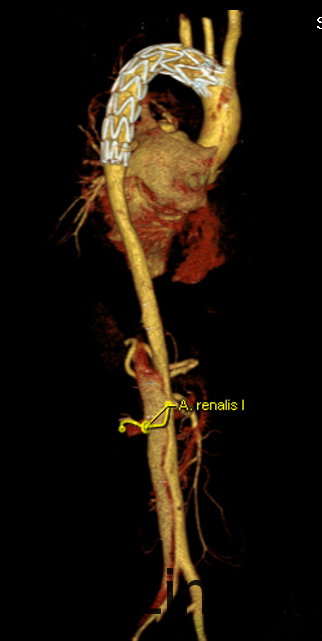

予以诊断:1.主动脉夹层动脉瘤;2.高血压3级,极高危组。诊断明确后行“左颈总动脉-腋动脉转流手术+胸主动脉覆膜支架腔内隔绝术”。左侧颈部切口,游离出左侧颈总动脉,左侧锁骨下动脉,左侧椎动脉等分支。使用8mmG-tex血管一端与左锁骨下动脉行端侧吻合,G-tex血管另一端与左侧颈总动脉行端侧吻合。经右侧股动脉入路造影见主动脉夹层,破口位于左锁骨下动脉开口医院0.5cm处。左锁骨下动脉近端封闭,桥血管通畅,腋动脉及左侧椎动脉血流良好。置入美敦力胸主动脉覆膜支架(28*157mm),定位后释放。造影见胸主动脉支架释放良好。

主动脉夹层为大血管急诊,B型主动脉夹层相对预后良好。保守治疗效果尚可,近期死亡率相对不高。但对于年轻患者,我们积极治疗。患者B型主动脉夹层,破口位于锁骨下动脉附近。拟行腔内修复术。但患者破口离锁骨下动脉较近,若直接封闭,可影响左上肢活动及椎动脉顺行血流。故根据患者情况行一期复合手术(即“左颈总动脉-腋动脉转流手术+胸主动脉覆膜支架腔内隔绝术”)。术后复查可及左侧锁骨下动脉通畅,血流灌注可。可及假腔内明显血栓化。